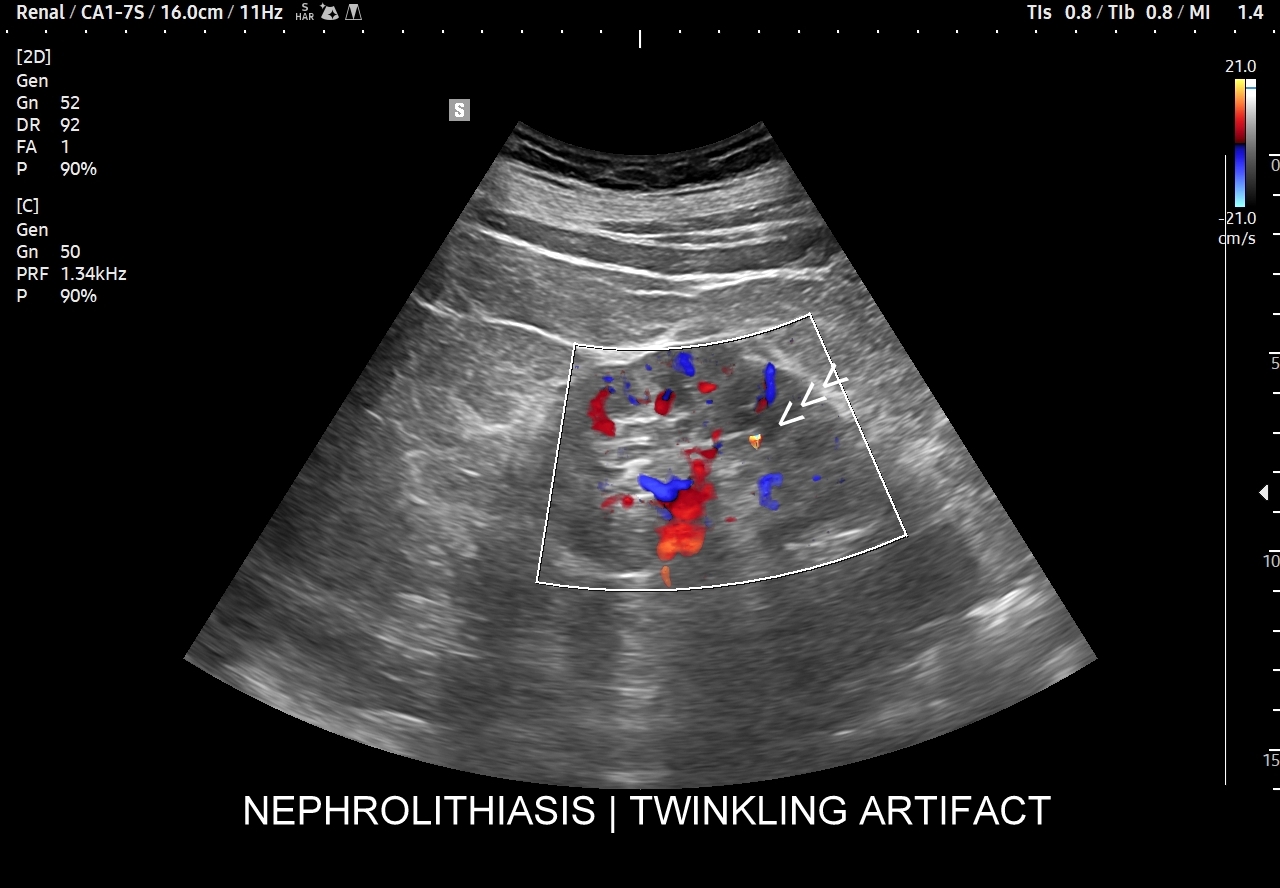

Ważnym trybem pomocniczym jest color-Doppler, w którym to trybie uzyskuje się tzw. artefakt migotania, często nawet na bardzo drobnych złogach niewidocznych w trybie B. Uzyskanie efektu migotania jest niestety zależne o jakości aparatury USG, a także od ustawień Dopplera i software’u.

Badania obrazowe służące wykrywaniu kamicy moczowej to badanie RTG, CT, lecz przede wszystkim badanie USG. W badaniu USG nerek w prezentacji B kamica nerkowa widoczna jest w sytuacji, gdy złogi są odpowiednio uwapnione, odpowiednio duże oraz nie zlewają się z zatoką tłuszczową miedniczki nerki. Zasadniczo złogi w trybie B będą widoczne wyraźniej, gdy położone są w miąższu nerki; z kolei w miedniczce nerkowej, gdy są na tyle duże, że dają artefakt cienia. Czasem w celu uwidocznienia złogu przydatne jest wyłączenie wspomagania typu x-beam.